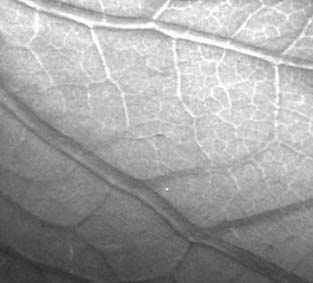

где a - угол между пучком и преломляющей поверхностью, n - показатель преломления, l - длина волны, выраженная в ангстремах. Величина рефракционного контраста определяется относительным локальным изменением интенсивности пучка, испытавшего отклонение на угол a. Для цилиндрического объекта наибольший контраст возникает на его краях, поэтому изображения кажутся объемными (см., например, рис.2). Подробный расчет контраста и дозы облучения для рефракционной интроскопии можно найти в [4].

Рис. 2. Изображение древесного листа,

полученное методом рефракционной интроскопии.